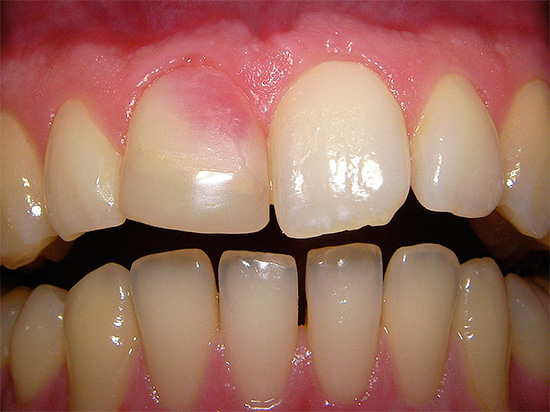

Domanda al dentista: "Perché il mio dente si oscura dopo aver rimosso un nervo?"

Dopo un trattamento di qualità dei canali, il dente di solito non si scurisce nel corso degli anni, ma diventa solo più scuro, cioè perde la sua lucentezza naturale, che non è una deviazione dalla norma.Se il dente diventa nero o giallo dopo un po 'di tempo dopo la rimozione del nervo, allora dovresti cercare la causa o nella preparazione della cavità del dente per il riempimento (in un'asportazione di scarsa qualità dei tessuti cariati) o in una scarsa elaborazione strumentale dei canali lasciando residui di nervi e infezione batterica in essi.

Inoltre, spesso un grave cambiamento nel colore della corona dentale è associato al materiale utilizzato per riempire i canali. Quindi, ad esempio, alcuni dentisti continuano a riempire per errore i canali dei denti anteriori dopo aver rimosso il nervo con Endometasone, per cui dopo alcuni anni i denti possono diventare molto gialli, il che è persino indicato nelle istruzioni per il materiale.

Tutte le sfumature del rosa possono apparire su un dente morto dopo aver riempito i canali con pasta di resorcinolo-formalina. Sfortunatamente, continuano ancora a usare questa pasta dannosa in tutti i sensi a un ricevimento di bilancio, soprattutto dopo aver rimosso i nervi da denti decidui.